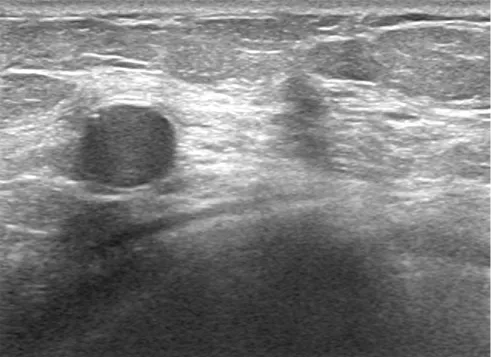

超音波検査は、豊胸後の乳がん検診において最も基本的かつ重要な検査です。

1)乳腺組織の観察:マンモグラフィでインプラントに隠れてしまう部分や、高濃度乳房の方の診断に特に優れています。

2)インプラントの状態評価: インプラントの破損、リーク、周囲の被膜拘縮の状態**をリアルタイムに確認するのに最も適しています。

3)脂肪注入後の評価:: 注入後のしこり(脂肪壊死)やオイルシストを詳細に観察し、乳がんとの鑑別に非常に有用です。